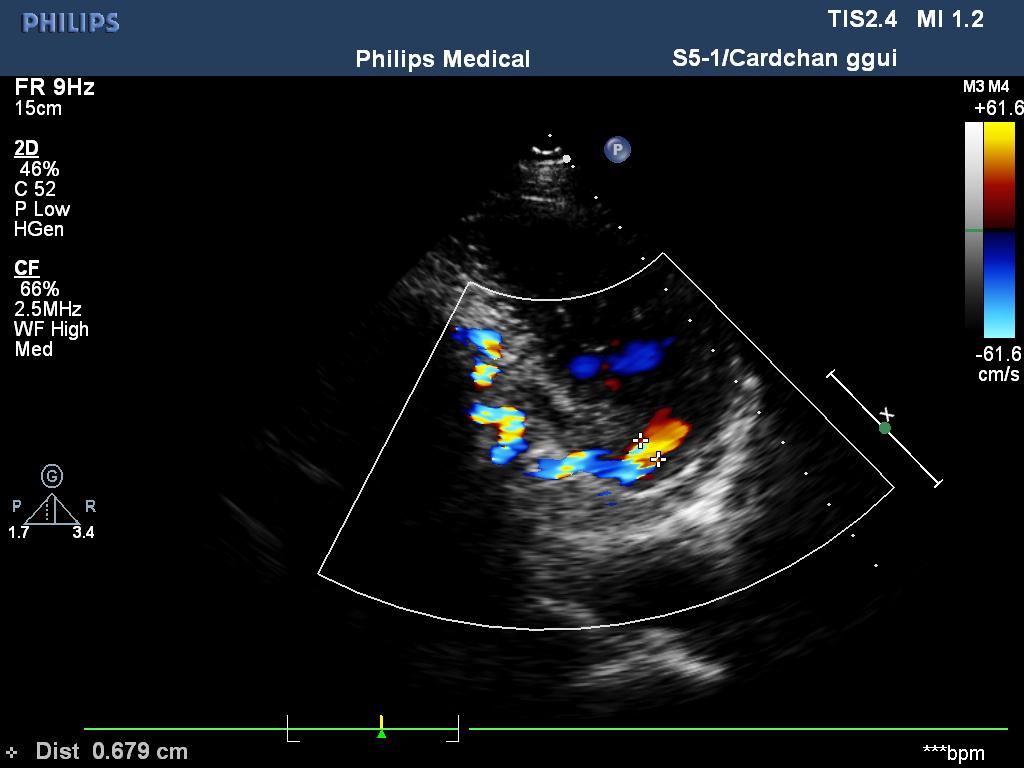

(右冠状动脉在左室内的瘘口)

超声所见:各房室大小及大动脉根部内径正常,各瓣膜回声正常,二尖瓣,三尖瓣及主动脉瓣开启可,关闭欠佳,余瓣膜启闭可。房、室间隔连续完整,室壁厚度及运动收缩幅度正常。右冠状动脉自主动脉起始处开始迂曲扩张,较宽处内径约10mm,于二尖瓣后叶瓣环处与左室相通,开口处内径约9mm。心包腔内未见明显液性暗区。CDFI:于二尖瓣后叶瓣环处探及舒张期异常血流信号,峰值流速1.85m/s。二尖瓣、三尖瓣口可见收缩期返流信号。主动脉瓣口可见舒张期返流信号。

超声提示:1.右冠状动脉左室瘘;2.右冠状动脉迂曲扩张;3.二尖瓣、三尖瓣、主动脉瓣少量返流;4.左室舒张功能减退。